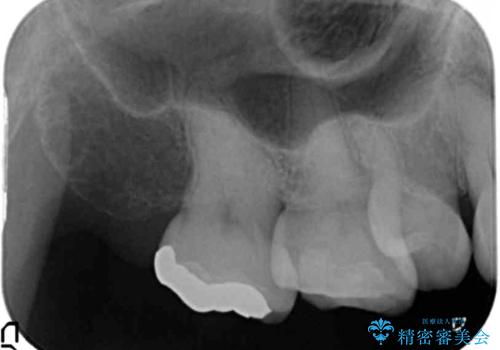

- 奥歯の詰め物のやり替えを希望して来院。

銀歯と、プラスチックをセラミックにかえました。

古い詰め物を取るときに、しっかり虫歯はとっています。

右上6番は詰め物が大きく、インレーではなくクラウンとしました。